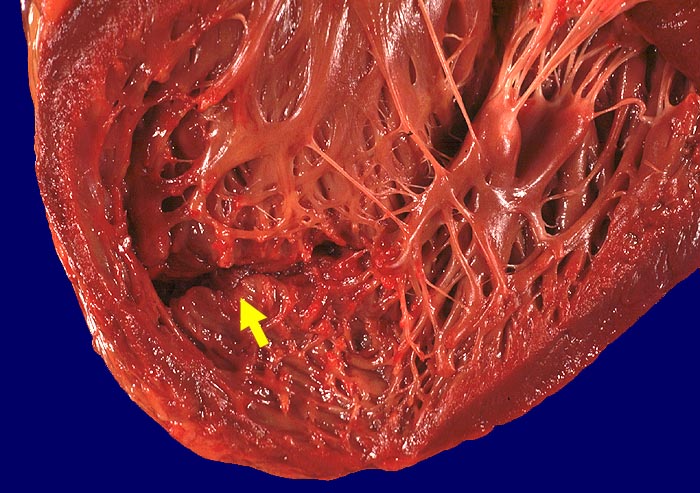

PathoPic ID 777 - Subakuter Myokardinfarkt des Septums mit Septumruptur

Schlitzförmige Ruptur im Herzseptum.

Subakuter Myokardinfarkt des Septums. Ruptur in den rechten Ventrikel.